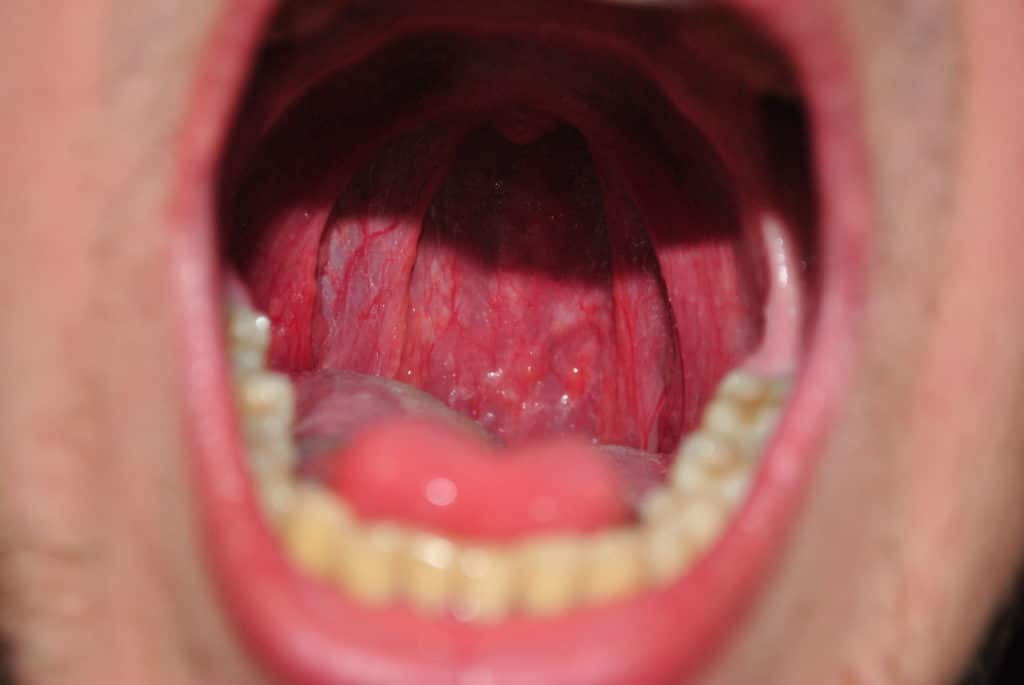

Во время первичного приема врач расспрашивает пациента о симптомах, образе жизни, вредных привычках, осматривает и ощупывает шею. Прямо в кабинете может быть проведена непрямая ларингоскопия: врач просит пациента открыть рот и осматривает гортань с помощью небольшого зеркальца, введенного через рот.

Обследование при раке горла начинается с наружного осмотра, во время которого доктор осторожно прощупывает область шеи, определяя наличие уплотнений и/или болезненности. Кроме того, в ходе первичной консультации специалист осматривает полость рта с помощью обычных ЛОР-инструментов.

В некоторых случаях обнаружить рак горла, получить материал для анализа под микроскопом и сделать первые выводы о стадии заболевания удается уже при проведении этих простых манипуляций. Однако чаще всего для уточнения диагноза требуется проведение дополнительного обследования.

В том числе, первичная диагностика рака горла включает детальный осмотр слизистой оболочки глотки и гортани с помощью эндоскопического оборудования. Если в процессе такого осмотра обнаруживаются подозрительные зоны, из них берутся фрагменты ткани для биопсии.

Непрямая ларингоскопия с помощью зеркальца определяют границы, локализацию, форму и приблизительные размеры опухоли.